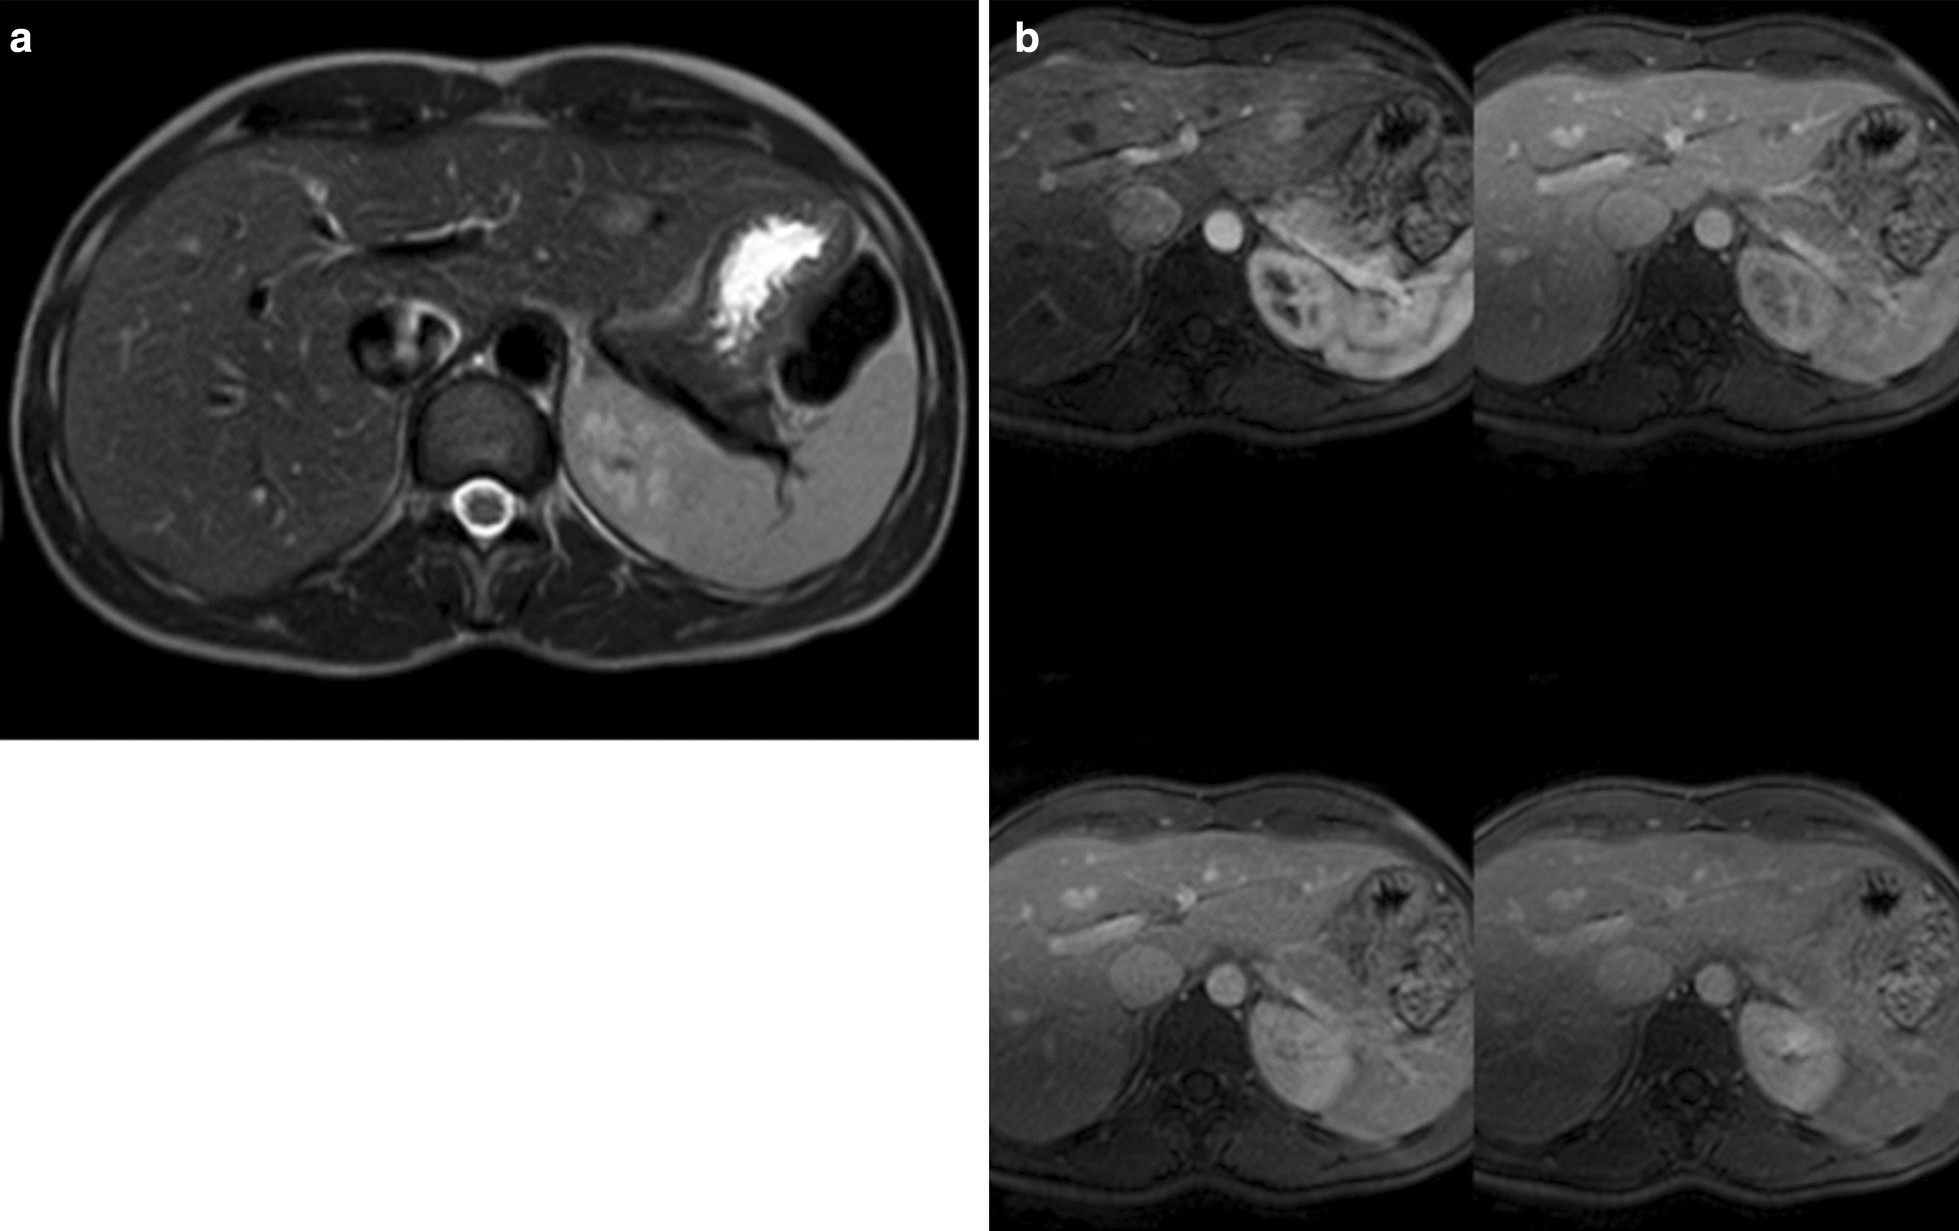

Fig. 2

a, b Abdominal magnetic resonance imaging. In segment 2 adjacent to the left portal branch and below the suprahepatic branch, a focal lesion of 18 mm was identified. The lesion is hypointense in T1, moderately hyperintense in T2 (a), although with poorly defined edges and with clear diffusion restriction. In the dynamic study, it is a hypervascular lesion in the arterial phase that washes in the portal and late phases (b)